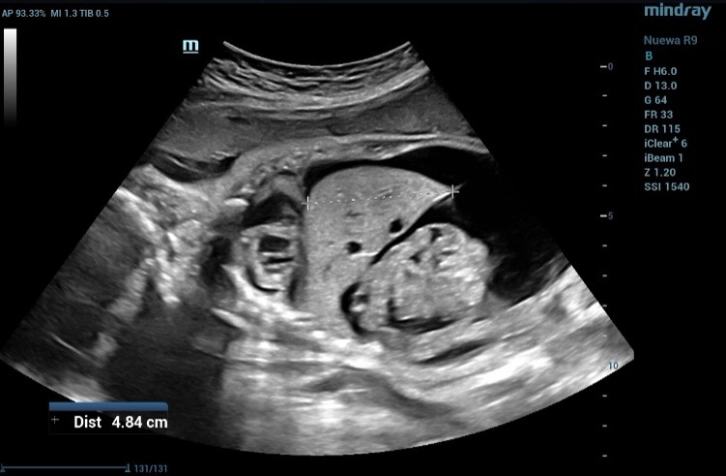

Fetal Biometric Measurements: Abdominal Circumference (AC)

Figure 3 Fetal Biometric Measurements: Abdominal Circumference (AC). AC is one of the basic biometric parameters used to assess fetal size

The measurement of Biparietal Diameter (BPD) (Figure 1) and Femur Length (FL) (Figure 2) demonstrated a close approximation to the actual gestational age. However, when assessing the Abdominal circumference (AC), it was observed that the measured gestational age exceeded the actual gestational age due to the presence of fluid accumulation around the fetal abdomen (Figure 3).